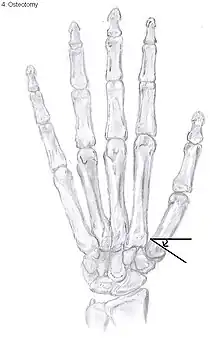

Osteotomy of the thumb

Metacarpal osteotomy

The aim of metacarpal osteotomy is to change the pressure distribution on the TMC joint. The hope is that this will slow the pace of development of osteoarthritis. There is no evidence that this procedure can modify the natural course of TMC OA. Osteotomy may be considered for people with mild arthritis.[20]

During osteotomy, the metacarpal is cut and a wedge shape bone fragment is removed to move the bone away from the hand.[31] Postoperative, the thumb of the patient is immobilized using a thumb-cast.

Possible complications are non-union of the bone, persistent pain related to unrecognized CMC or pantrapezial disease and radial sensory nerve injury.[20]